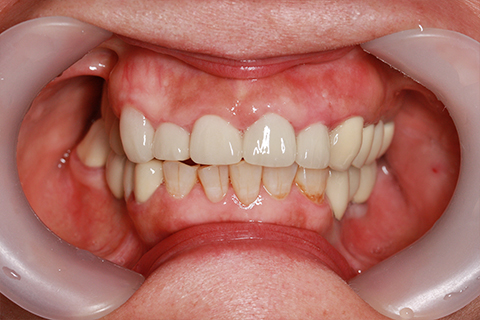

症例5

- 年齢・性別

- 35歳男性

- 治療期間

- 3ヶ月

- 抜歯

- 右上1.3左上6.7の残根抜歯

- 治療費

- 132万円

- 備考

- 右上1.3左上6.7の欠損部

- 治療内容

- 4本のインプラントを一回のオペで埋入。

- 施術の副作用(リスク)

- オペによる知覚障害。インプラントによる歯肉炎。インプラント脱落。